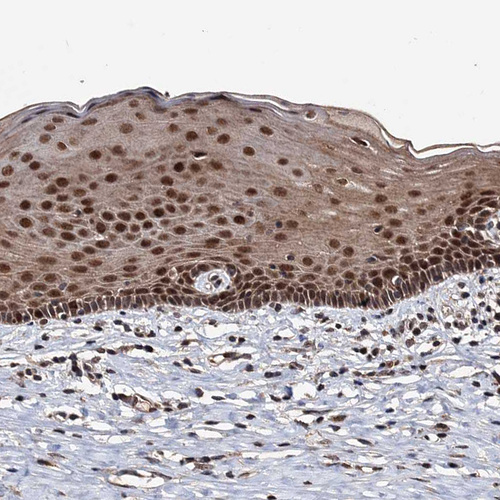

Immunohistochemical staining of human cervix, uterine shows strong nuclear positivity in squamous epithelial cells.